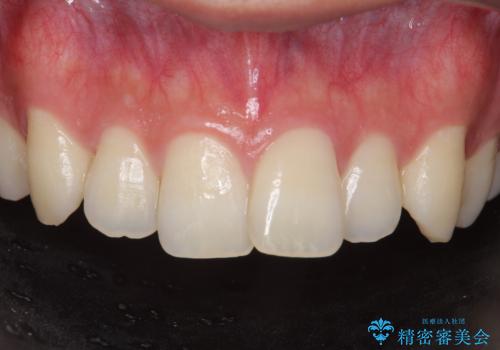

前歯を綺麗にしたい。

- 前歯を良くしたい(綺麗にしたい)との事で来院。

のご提案をしたところ2のプランを選択されたのでセラミック治療を行いました。

- ジルコニアクラウンスペシャル・仮歯 16.5万円×2 精密根管治療(イニシャルトリートメント)・ファイバーコア 8.8万円費用は治療当時の料金となります

見た目が良くなり大変満足して頂けました。